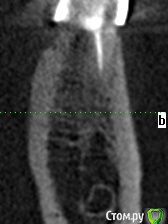

meld Опубликовано 7 ноября, 2017 Поделиться Опубликовано 7 ноября, 2017 Здравствуйте! Чуть больше года назад заболел 36 зуб. Я его пролечил с диагнозом периодонтит. 37 зуба нет. Было принято решение поставить мост с опорой на 36 и 38 зубы. 38 зуб был депульпирован в январе 2017 г. В мае 2017 я поставил мост. Вчера 38 зуб стал болеть при жевании. Боль не сильная, ломящая, через некоторое время проходит. Сегодня съездил в клинику, где лечил зубы, на осмотр. Осмотр ничего не выявил. Сделали прицельный снимок - по словам врачей (а их было двое) криминала тоже нет. Показал им свою томограмму - там тоже (по их словам) ничего нет. Посмотрите, пожалуйста, что не так. СпасибоСрезы 36 зуба Ссылка на комментарий